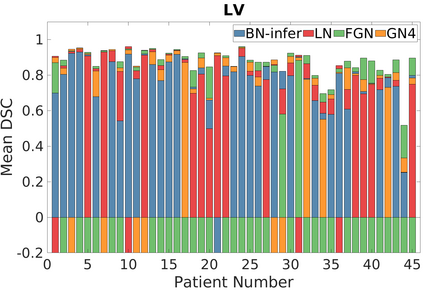

Deep Convolutional Neural Networks (DCNNs) are used extensively in biomedical image segmentation. However, current DCNNs usually use down sampling layers for increasing the receptive field and gaining abstract semantic information. These down sampling layers decrease the spatial dimension of feature maps, which can be detrimental to semantic image segmentation. Atrous convolution is an alternative for the down sampling layer. It increases the receptive field whilst maintains the spatial dimension of feature maps. In this paper, a method for effective atrous rate setting is proposed to achieve the largest and fully-covered receptive field with a minimum number of atrous convolutional layers. Furthermore, different atrous blocks, shortcut connections and normalization methods are explored to select the optimal network structure setting. These lead to a new and full-scale DCNN - Atrous Convolutional Neural Network (ACNN), which incorporates cascaded atrous II-blocks, residual learning and Fine Group Normalization (FGN). Application results of the proposed ACNN to Magnetic Resonance Imaging (MRI) and Computed Tomography (CT) image segmentation demonstrate that the proposed ACNN can achieve comparable segmentation Dice Similarity Coefficients (DSCs) to U-Net, optimized U-Net and hybrid network, but with significantly reduced trainable parameters due to the use of full-scale feature maps and therefore computationally is much more efficient for both the training and inference.